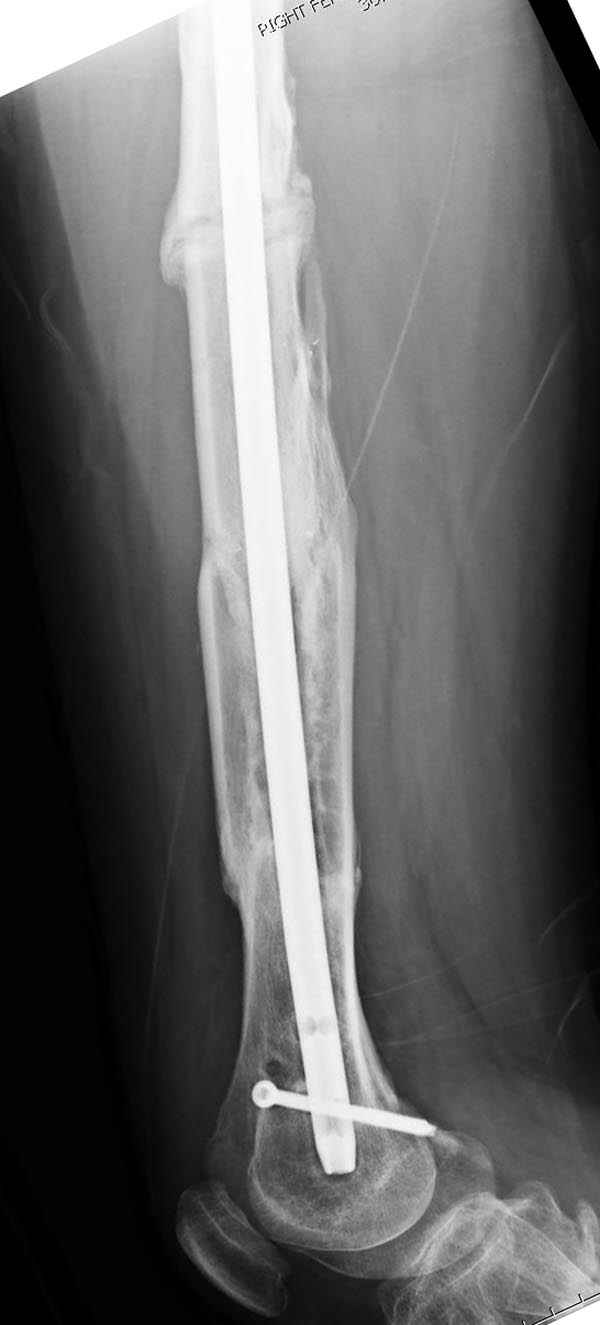

Представляю снимки больного с политравмой: леченного в другом мед.учреждении по поводу открытого перелома бедра, сперва аппаратом наружной фиксации, затем пластиной. Обратился к нам через 8 месяцев после удаления пластины с проблемой несросщего перелома бедренной кости, без клинических проявлении к инфицированию (не все снимки сохранены)

Рутинный интрамедуллярный остеосинтез с расверливанием и с фиксацией реконструктивным трокантерик штифтом (рис №1, №2),

если первые 4 месяца послеоперационного периода проходил без проблем, но на 5 месяце появились боли в дистальном отделе бедра и температура, т.е. симптомы медуллярного инфицирования (рис №3, №4).